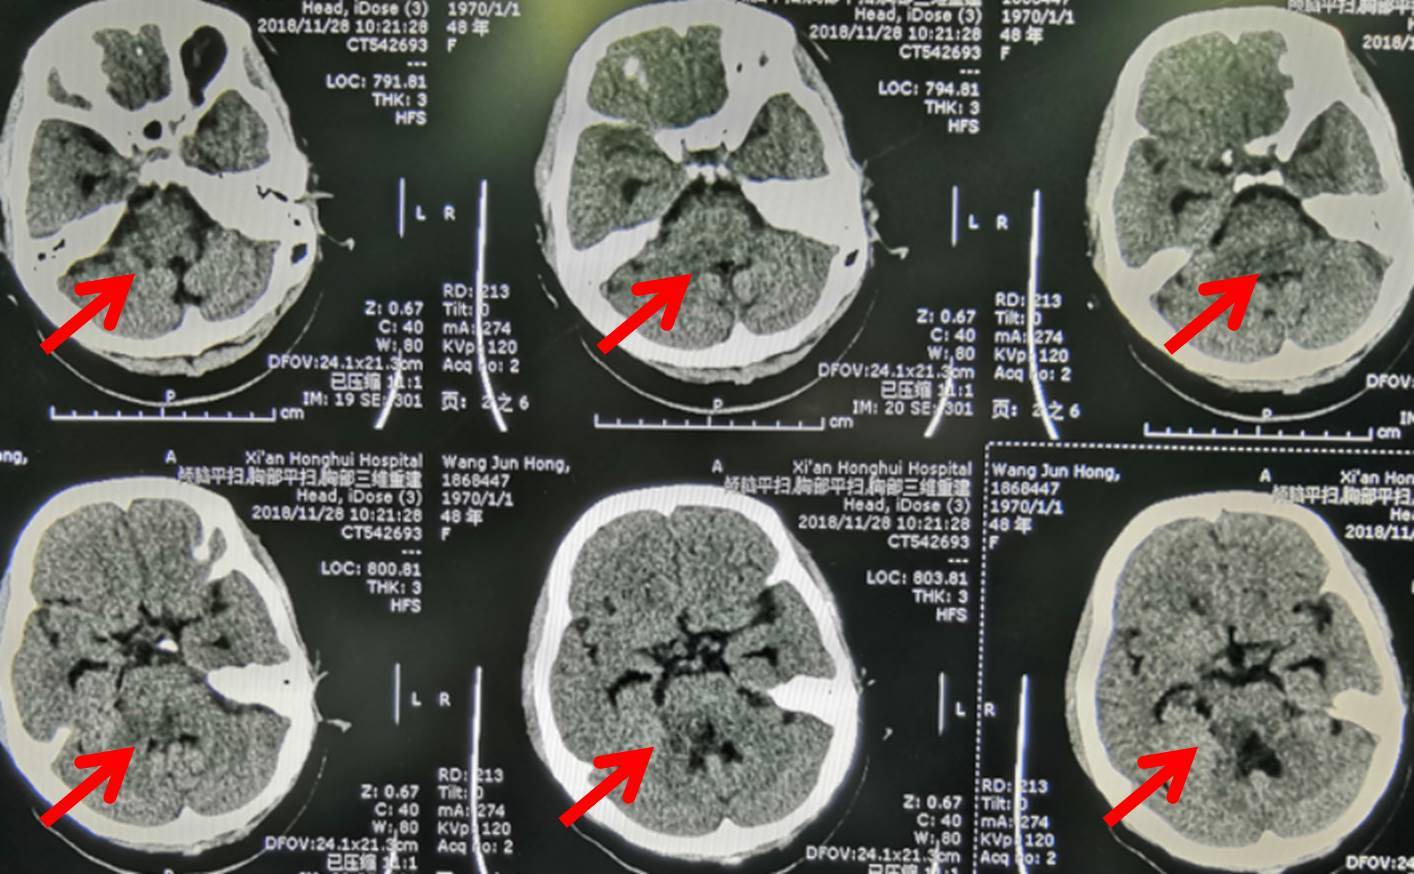

女子同房后“血崩”,差点丢命!原因竟是……